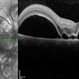

- preeclampsia, choroidal infarction

- 66-year-old Hispanic female with a history of severe preeclampsia at age 45. This photograph shows faint gray choroidal scars. Seen better on FA (in gallery).